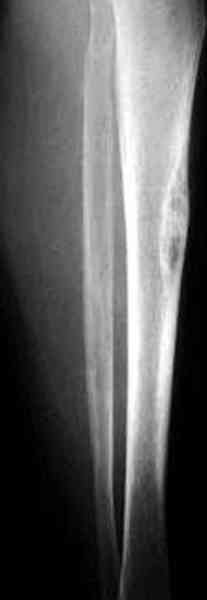

Недавно на нашей ежемесячной Morbidity&Mortality

conference мы разбирали похожий случай, ложный сустав большеберцовой кости после резекции опухоли.

К нашему онкологу-ортопеду обратился больной с жалобами на боли в голени, из рассказа - год назад была сделана биопсия большеберцовой кости, но название заболевания "не запомнил”.

Оперирован в военном госпитале с заменой сегмента

аллокостью большеберцовой кости и после демобилизации явился для постоянного наблюдения по месту жительства.

В литературе "A Classic Adamantinoma Arising from

Osteofibrous Displasialike Adamantinoma in the Lower Leg: A case report and Review of the Literature похожие снимки.

Наши имели проблему со сращением, пришлось им сделать динамизацию, дополнительную аутопластику.

Снимки представлены.